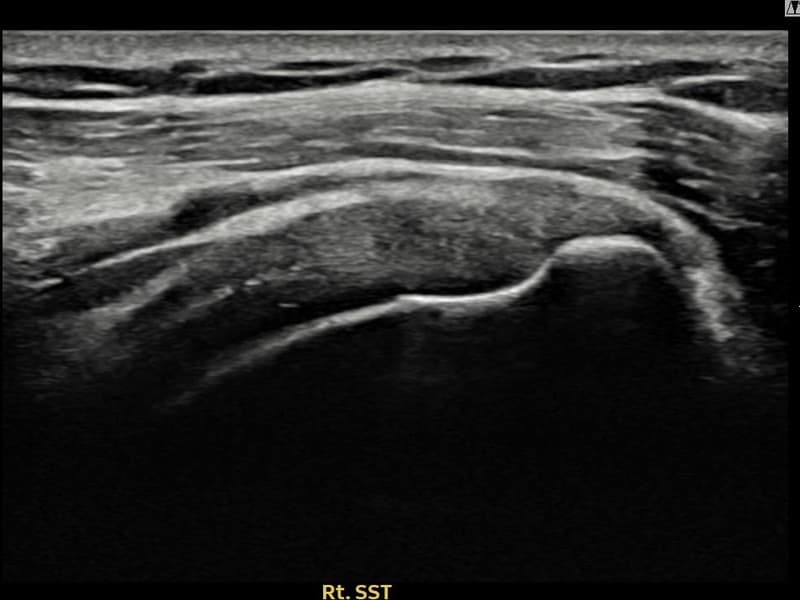

术后

术前超声确认右侧 冈上肌腱 关节面侧部分撕裂,右侧冈上肌腱回声不连续伴肌腱缺损(10mm × 4mm (肌腱厚度约40%缺损))。术后超声显示撕裂部位充满再生组织,肌腱连续性恢复,回声模式正常化。